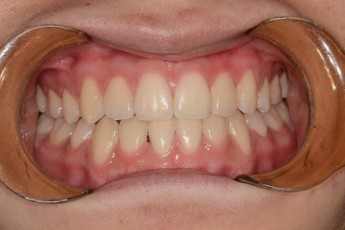

Before

After